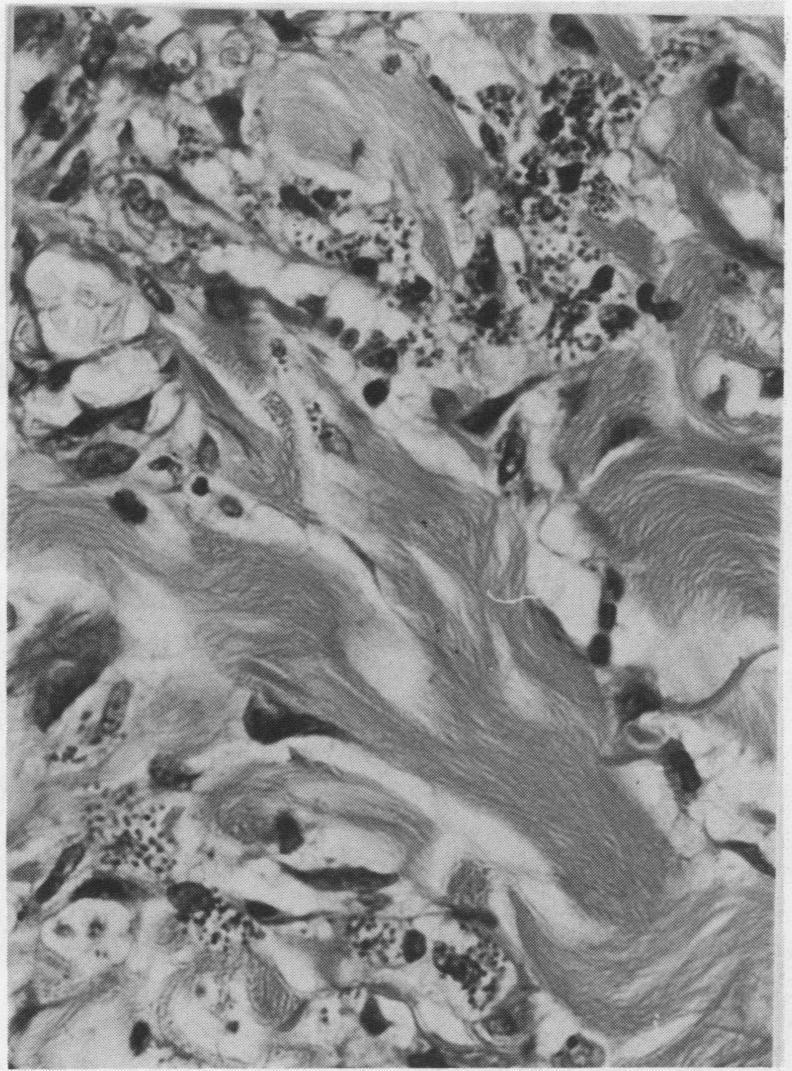

Opportunistic protozoan infections in human immunodeficiency virus disease: review highlighting diagnostic and therapeutic aspects.

摘要